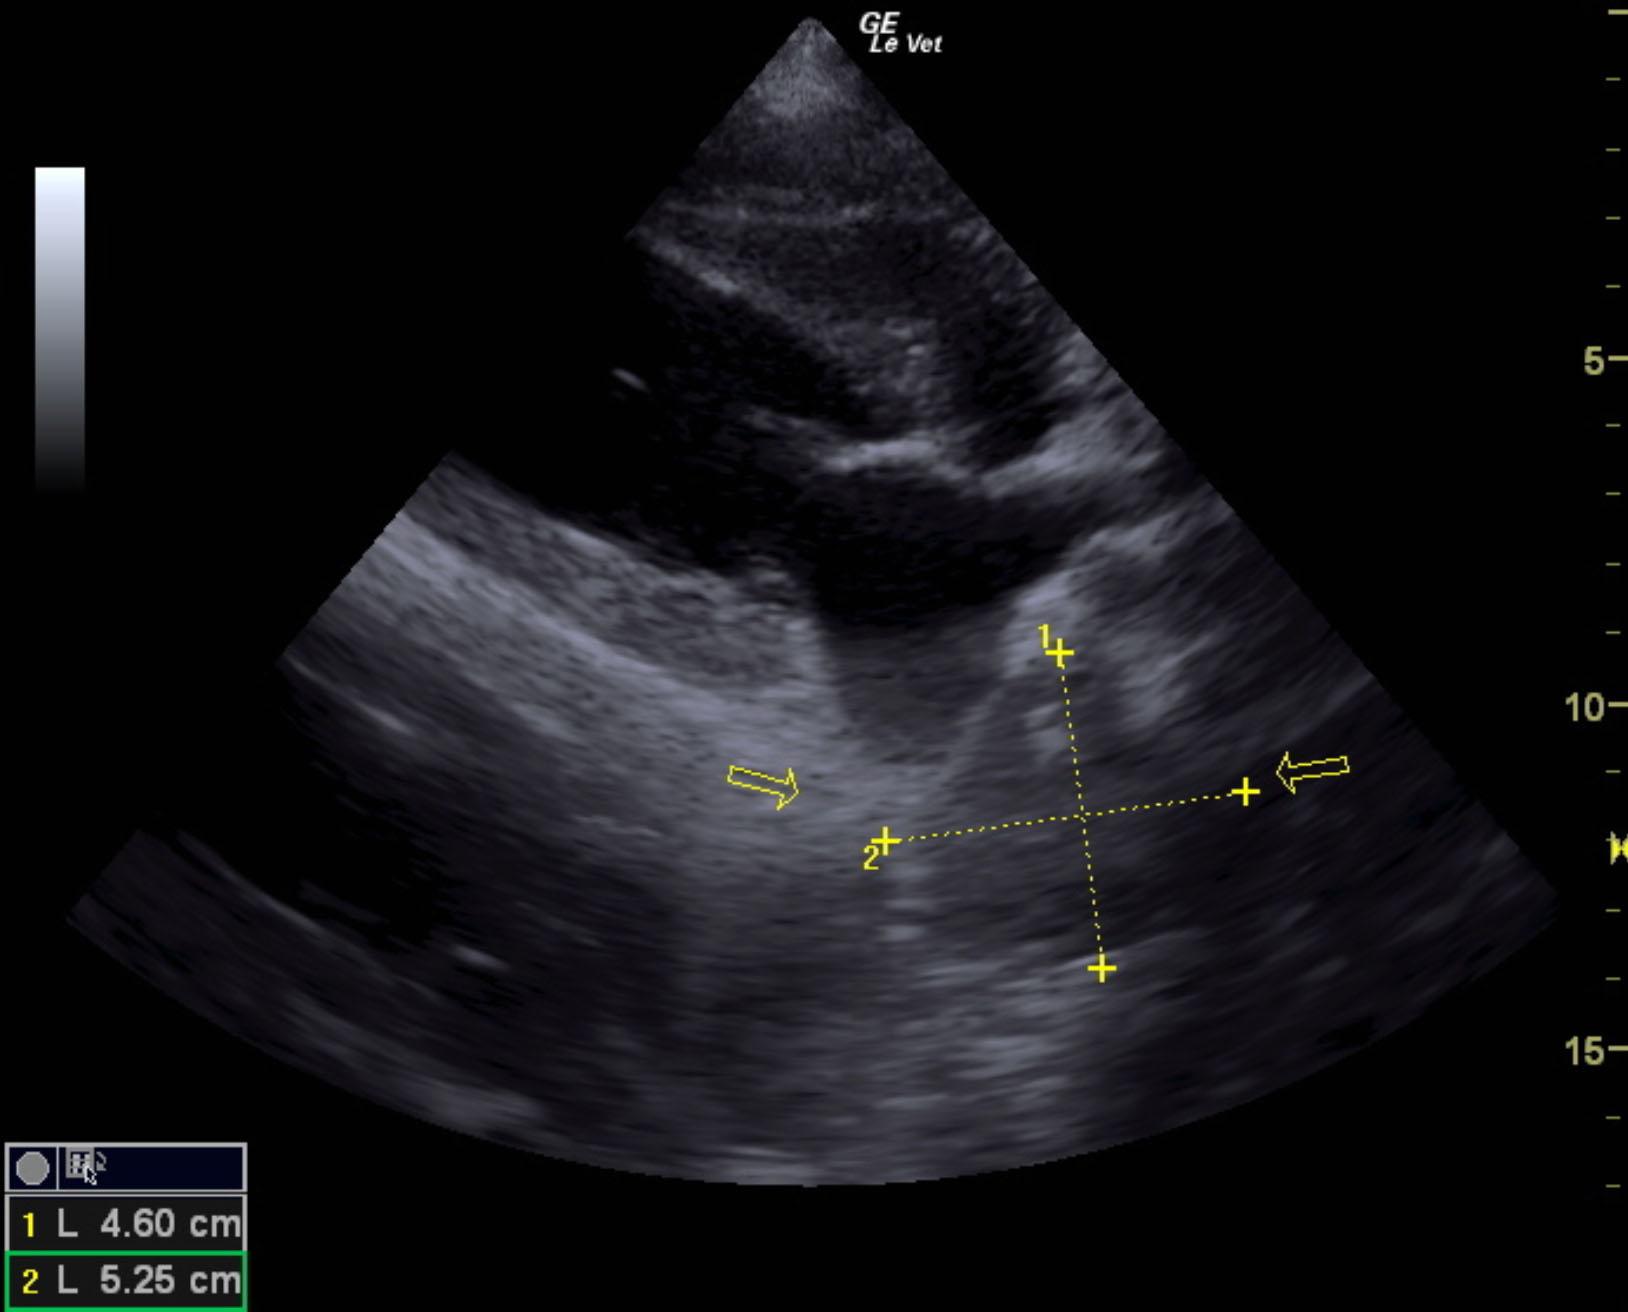

The patient is a canine Mastiff, male, 1 year old who was presented for surgery for the eye, however physical exam revealed muffled heart sounds. Radiographs revealed mass at the heart base.